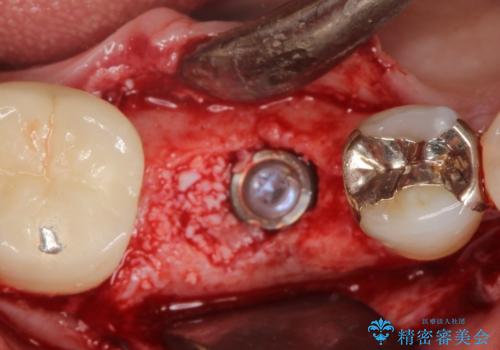

骨が成熟するまで待ち、インプラントを埋入しました。